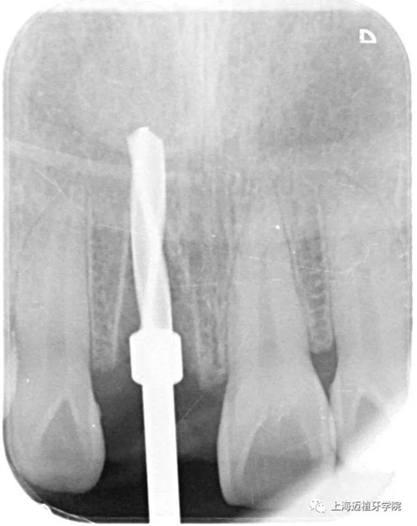

放置平行桿

CR片